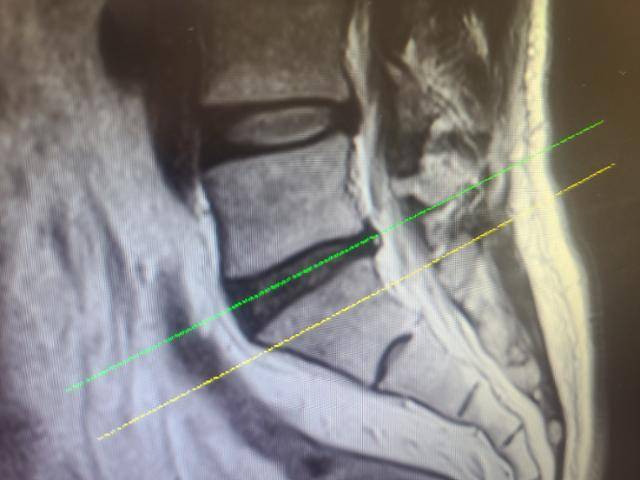

디스크 이상유무를 확인하는 방법은 CT촬영으로 인대 관련 증상을 확인하고 MRI촬영을 통해 디스크 전체의 상태를 확인해야 한다. 특히 MRI의 경우 척추와 디스크의 밀도와 디스크의 상태를 가장 정확하게 알 수 있다.